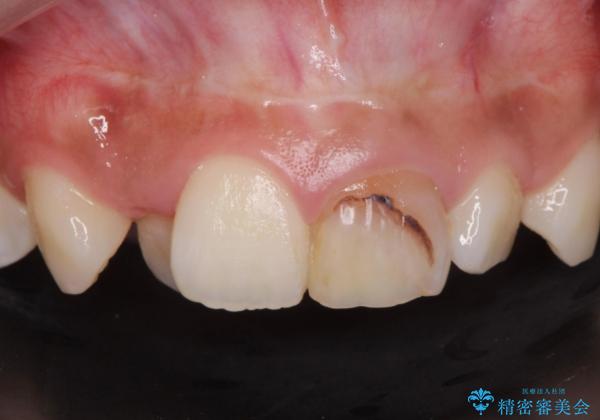

前歯の見た目が気になる。

- 前歯の見た目が気になるとの事で来院。

根の治療のやりかえは希望されなかったので土台だけやりかえを行い、ジルコニアクラウンで治療を行いました。